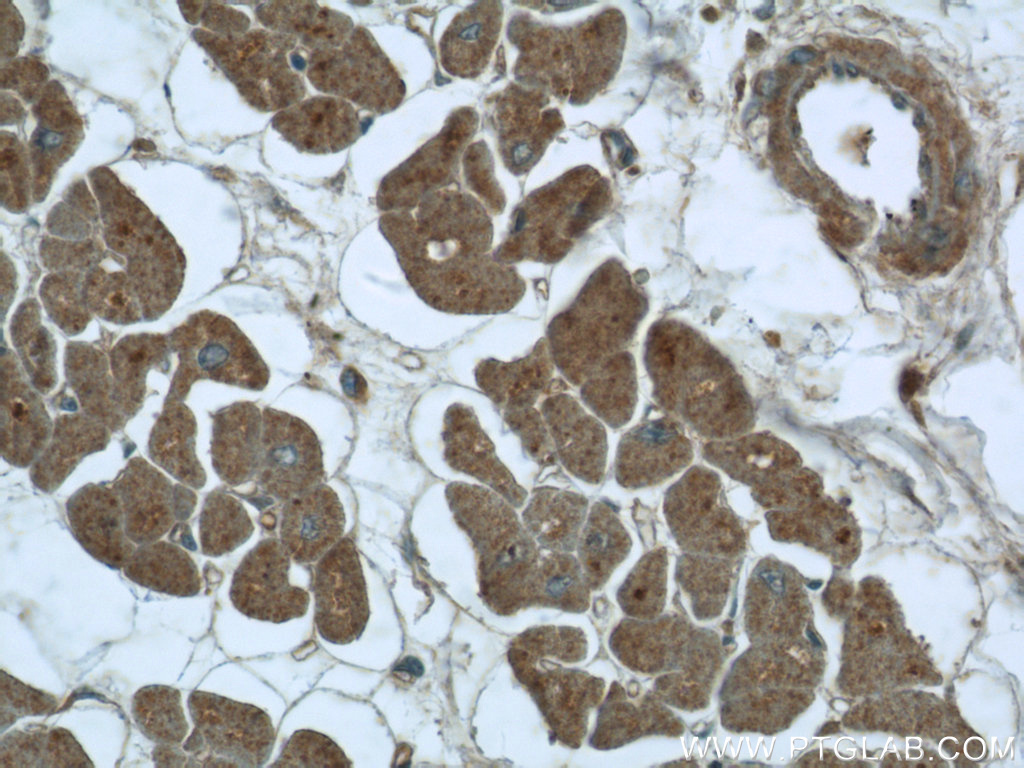

| Positive IHC detected in | human colon tissue, human heart tissue Note: suggested antigen retrieval with TE buffer pH 9.0; (*) Alternatively, antigen retrieval may be performed with citrate buffer pH 6.0 |

| Immunohistochemistry (IHC) | IHC : 1:100-1:1200 |